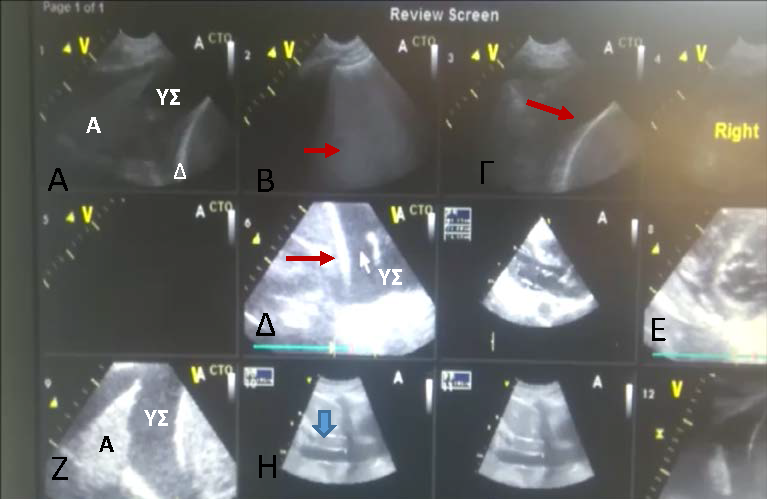

με φυσιολογική τιμή <17mm.[20] Εικ.4 Διαθωρακική υπερηχοκαρδιογραφία.

Κορυφαία λήψη 5 κοιλοτήτων σε ασθενή με ενδοκαρδίτιδα. Αναγνωρίζονται

ευμεγέθεις εκβλαστήσεις στην μιτροειδή βαλβίδα (λευκό βέλος) και στην

τριγλώχινα βαλβίδα (κόκκινο βέλος) Με